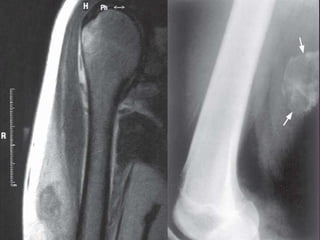

Miositis Osificante.

Presencia de hueso metaplásico.

Músculos proximales de las extremidades.

Adolescentes deportistas y adultos jóvenes tras un traumatismo en

más del 50% de los casos.

Fase temprana: Zona afectada tumefacta y dolorosa.

 En las siguientes semanas se hace circunscrita y dolorosa.

Por último se convierte en una masa bien delimitada e indolora.

 La miositis osificante es un proceso poco frecuente que no afecta al

hueso sino al músculo adyacente.

 Las lesiones pueden llegar a medir varios centímetros.

 Se produce una zona central de tejido de granulación exuberante y

muy celular, que puede imitar a un sarcoma.

 Los hallazgos radiológicos sugieren el diagnóstico correcto.

 A diferencia de una auténtica neoplasia, esta lesión disminuye de

tamaño con el tiempo.

 Puede causar dolor e irritación local